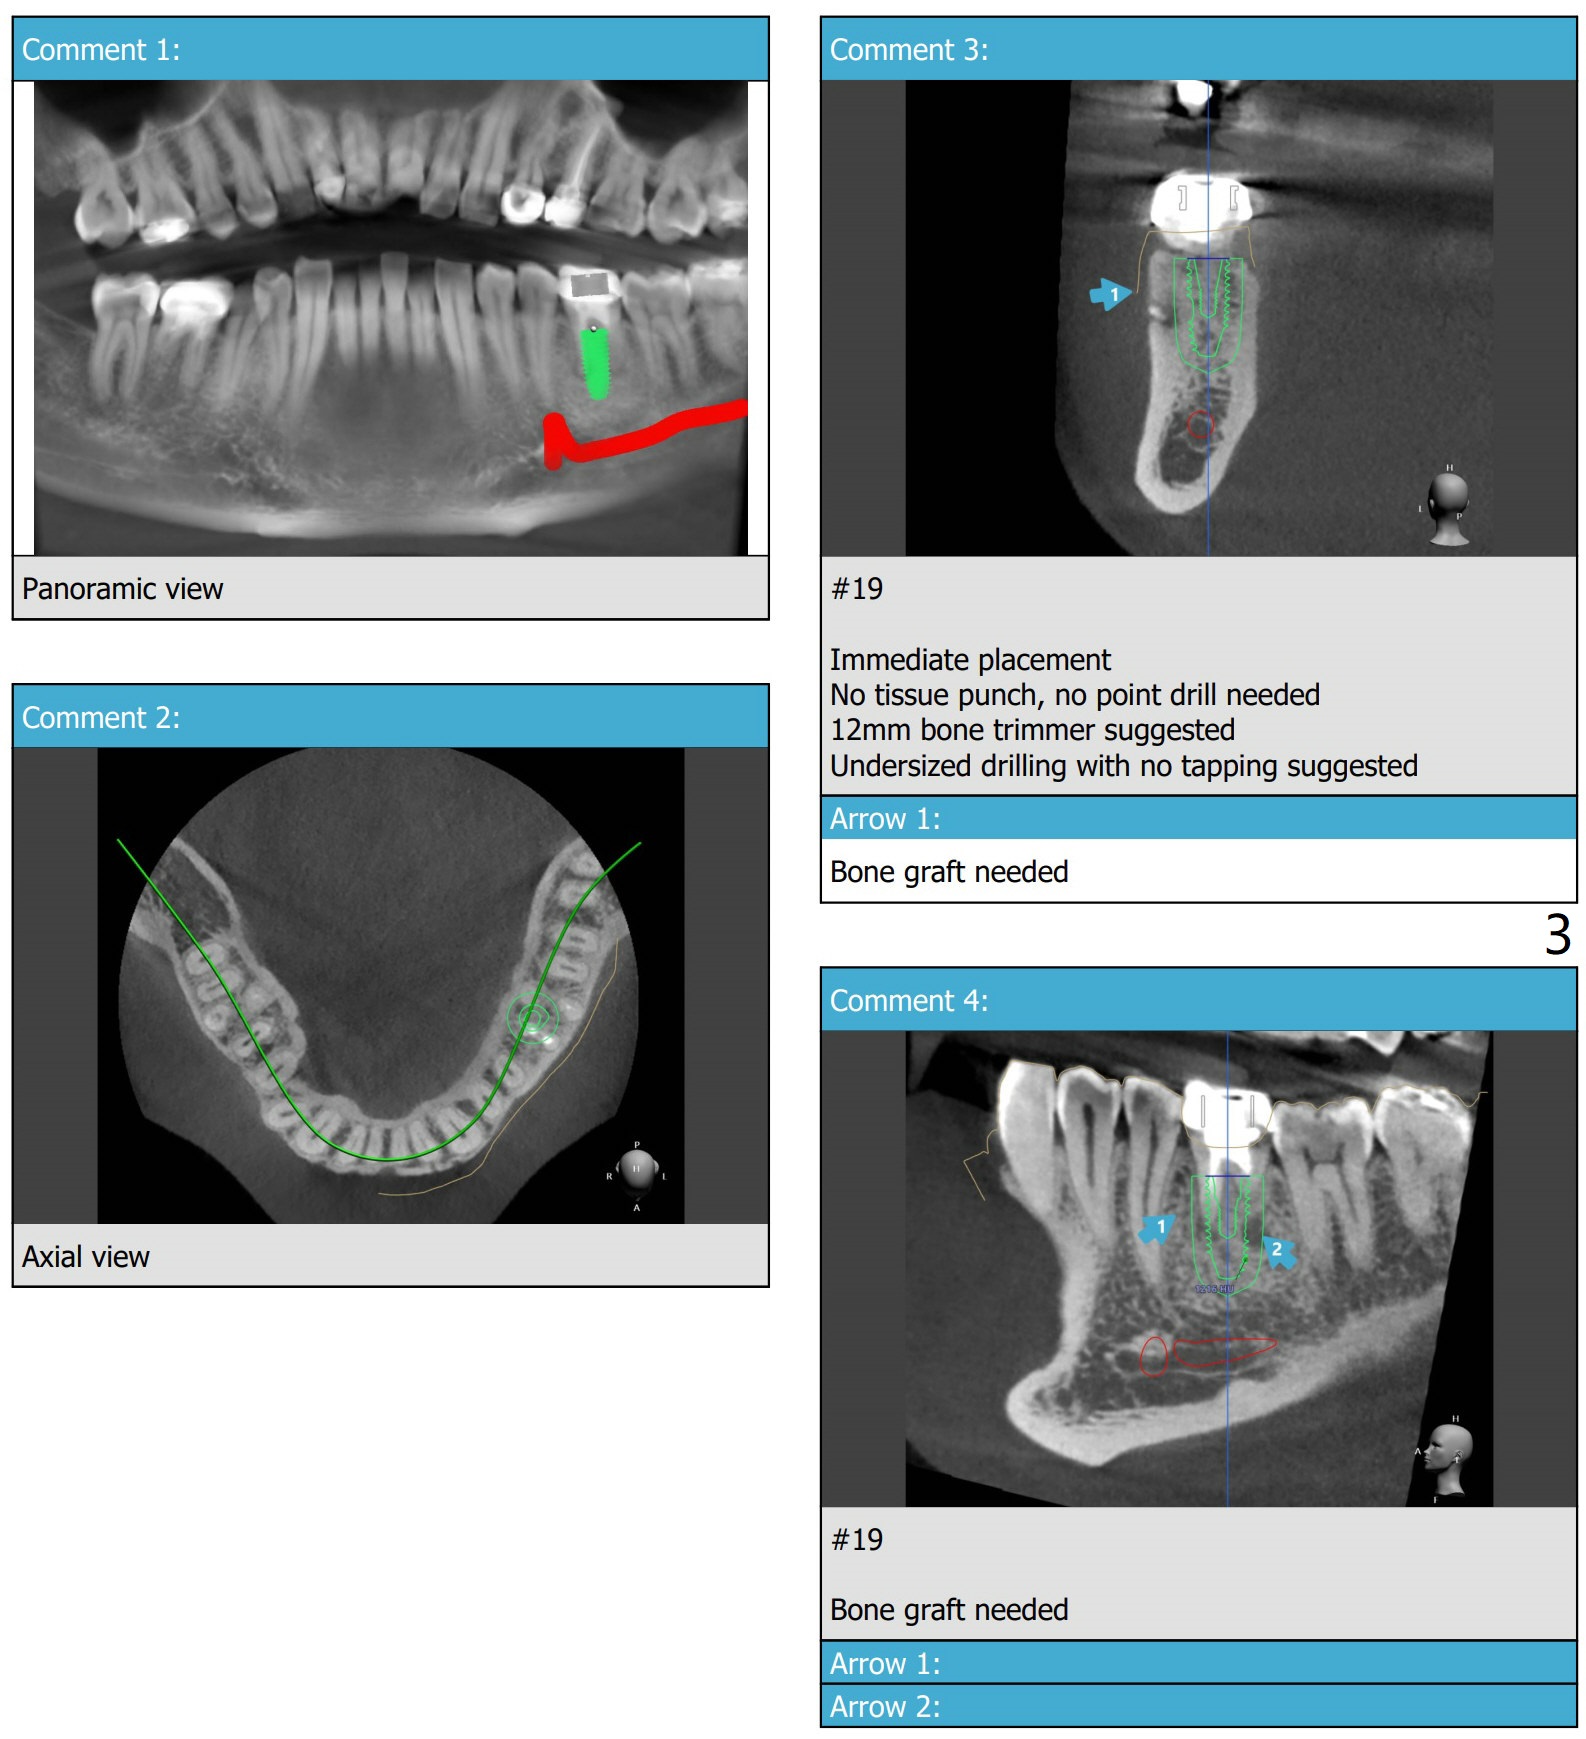

A 54-year-old man decides to extract the tooth #19 because of failure of RCT in the disto-lingual long curved root. Since it is difficult to drill through the roots, the latter will be removed. Use 2.2 mm drill to reach the depth first, look for deviation and take PA. Prepare cowhorn, surgical handpiece and proximators. PRFx1. Use 4.5x11.5 mm drill before placing 5.5x11mm IBS implant.